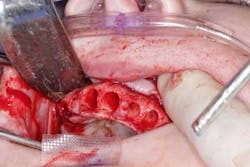

Surgery commenced. Implants on the lower arch were placed first (figures 7 and 8) and then we switched to the maxillary. The teeth were removed (figures 9 and 10) and the ridge was evened out (figures 11-13). The implants were aligned with the denture (figure 14) and then placed accordingly (figures 15-17). Healing caps were put on, and we were ready to start the restorative phase (figures 18-19).